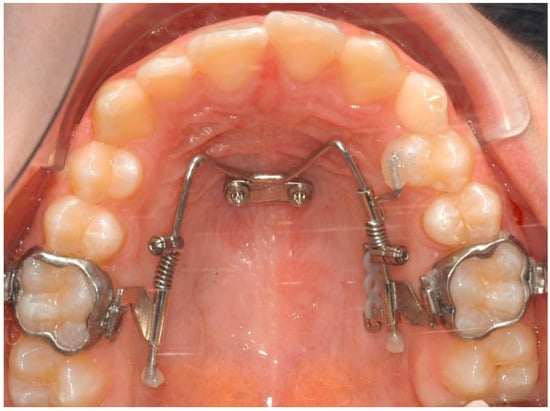

2.1. The Appliance

2.3. Case Description